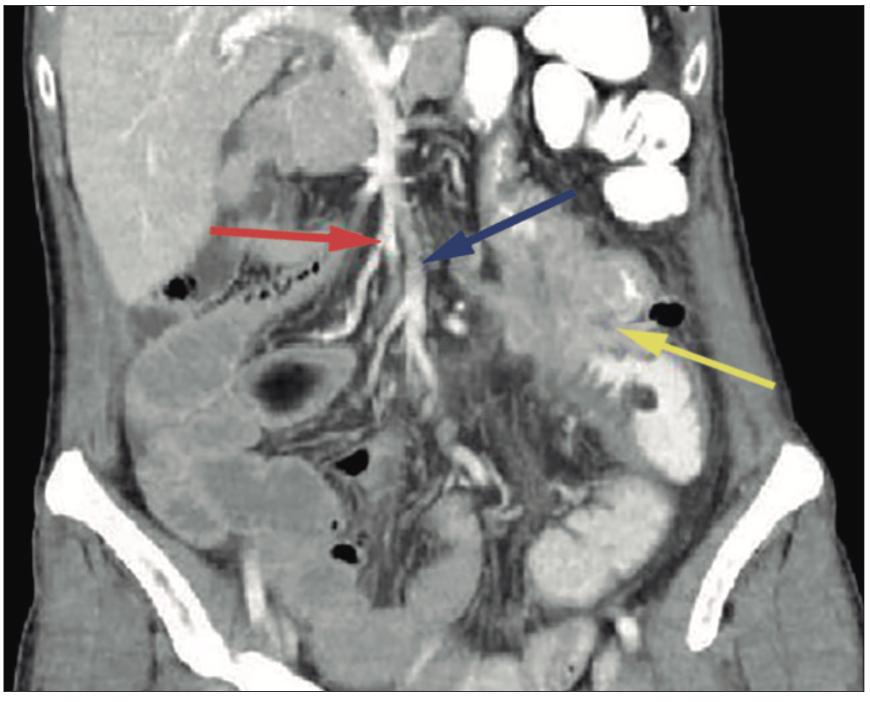

A 64-year-old woman with a medical history suggestive of iron deficiency anemia was referred after video colonoscopy reveled an adenocarcinoma of the right colon. CT staging revealed an intestinal malrotation, characterized by an ectopic cecum located on the left with the entire small bowel on the right and the colon on the left. In addition, there was a mass in the right colon. Figure 1.

Figure 1. Computed tomography showing intestinal malrotation and right-sided

colon cancer. Note the duodenum and small intestine to the right of the midline, the cecum to the left of

the midline with a tumor. There is an abnormal disposition of the mesenteric vessels with the superior

mesenteric vein anterior and to the left of the superior mesenteric artery. Red arrow: superior mesenteric

artery, Blue arrow: superior mesenteric vein, yellow arrow: right colonic tumor